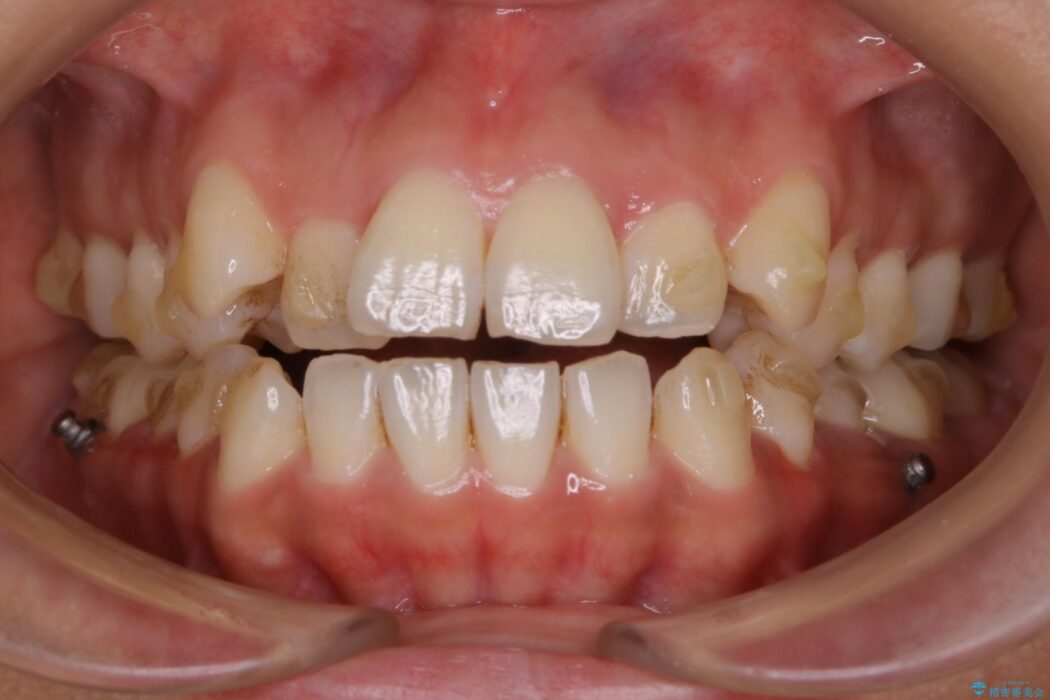

【20代女性】開咬の隙間と歯列の凸凹をまとめて改善する

開咬により上下の噛み合わせが悪く、歯列の凸凹も合わせて治療したいとのことで来院されました。

きちんと装着時間を守っていただいたこともあり、きれいな歯並びを獲得できました。